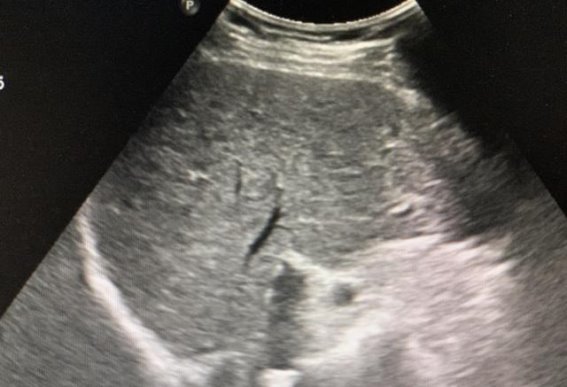

接着,肝病也是一类威胁生命的重大疾病,尤其是肝硬化和肝癌。肝脏是人体的重要器官,负责解毒、代谢和营养储存等多项功能。肝脏出现严重问题时,身体的其他功能也会受到影响。肝硬化早期通常没有明显症状,很多人忽视了这一潜在的健康风险。随着病情的发展,患者可能会出现黄疸、腹水、食欲减退等症状,肝功能逐渐丧失,最终可能发展为肝癌。肝癌的早期诊断相对困难,许多患者在就医时已经进入晚期,治疗效果大打折扣。通过定期体检,尤其是肝功能检查,可以在肝脏问题初现端倪时及时干预,避免病情恶化。对于高危人群,如长期饮酒、乙肝或丙肝感染者,定期进行肝脏超声检查,甚至CT或肝活检,是及早发现问题的有效途径。

肾脏疾病,尤其是终末期肾病,也是一类严重影响健康的疾病。肾脏是人体重要的排泄和代谢器官,负责排除废物和调节体内水电解质平衡。慢性肾病早期通常没有明显症状,患者可能感到一切正常,直到病情逐渐恶化,肾功能下降,才出现浮肿、高血压、尿量变化等症状。终末期肾病往往需要透析治疗,但透析无法完全代替肾脏的正常功能,患者的生活质量大大下降,甚至面临生命威胁。通过定期体检,尤其是检测血清肌酐、尿液分析和肾脏超声等检查,可以在早期发现肾脏功能的异常,及时采取治疗措施,防止病情进展到终末期。对于糖尿病、高血压等高危人群,定期检查肾功能显得尤为重要。